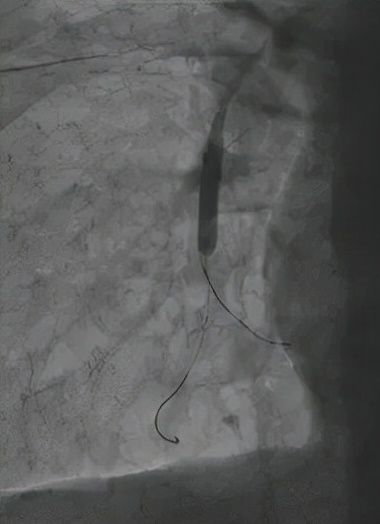

△球囊擴張狹窄血管